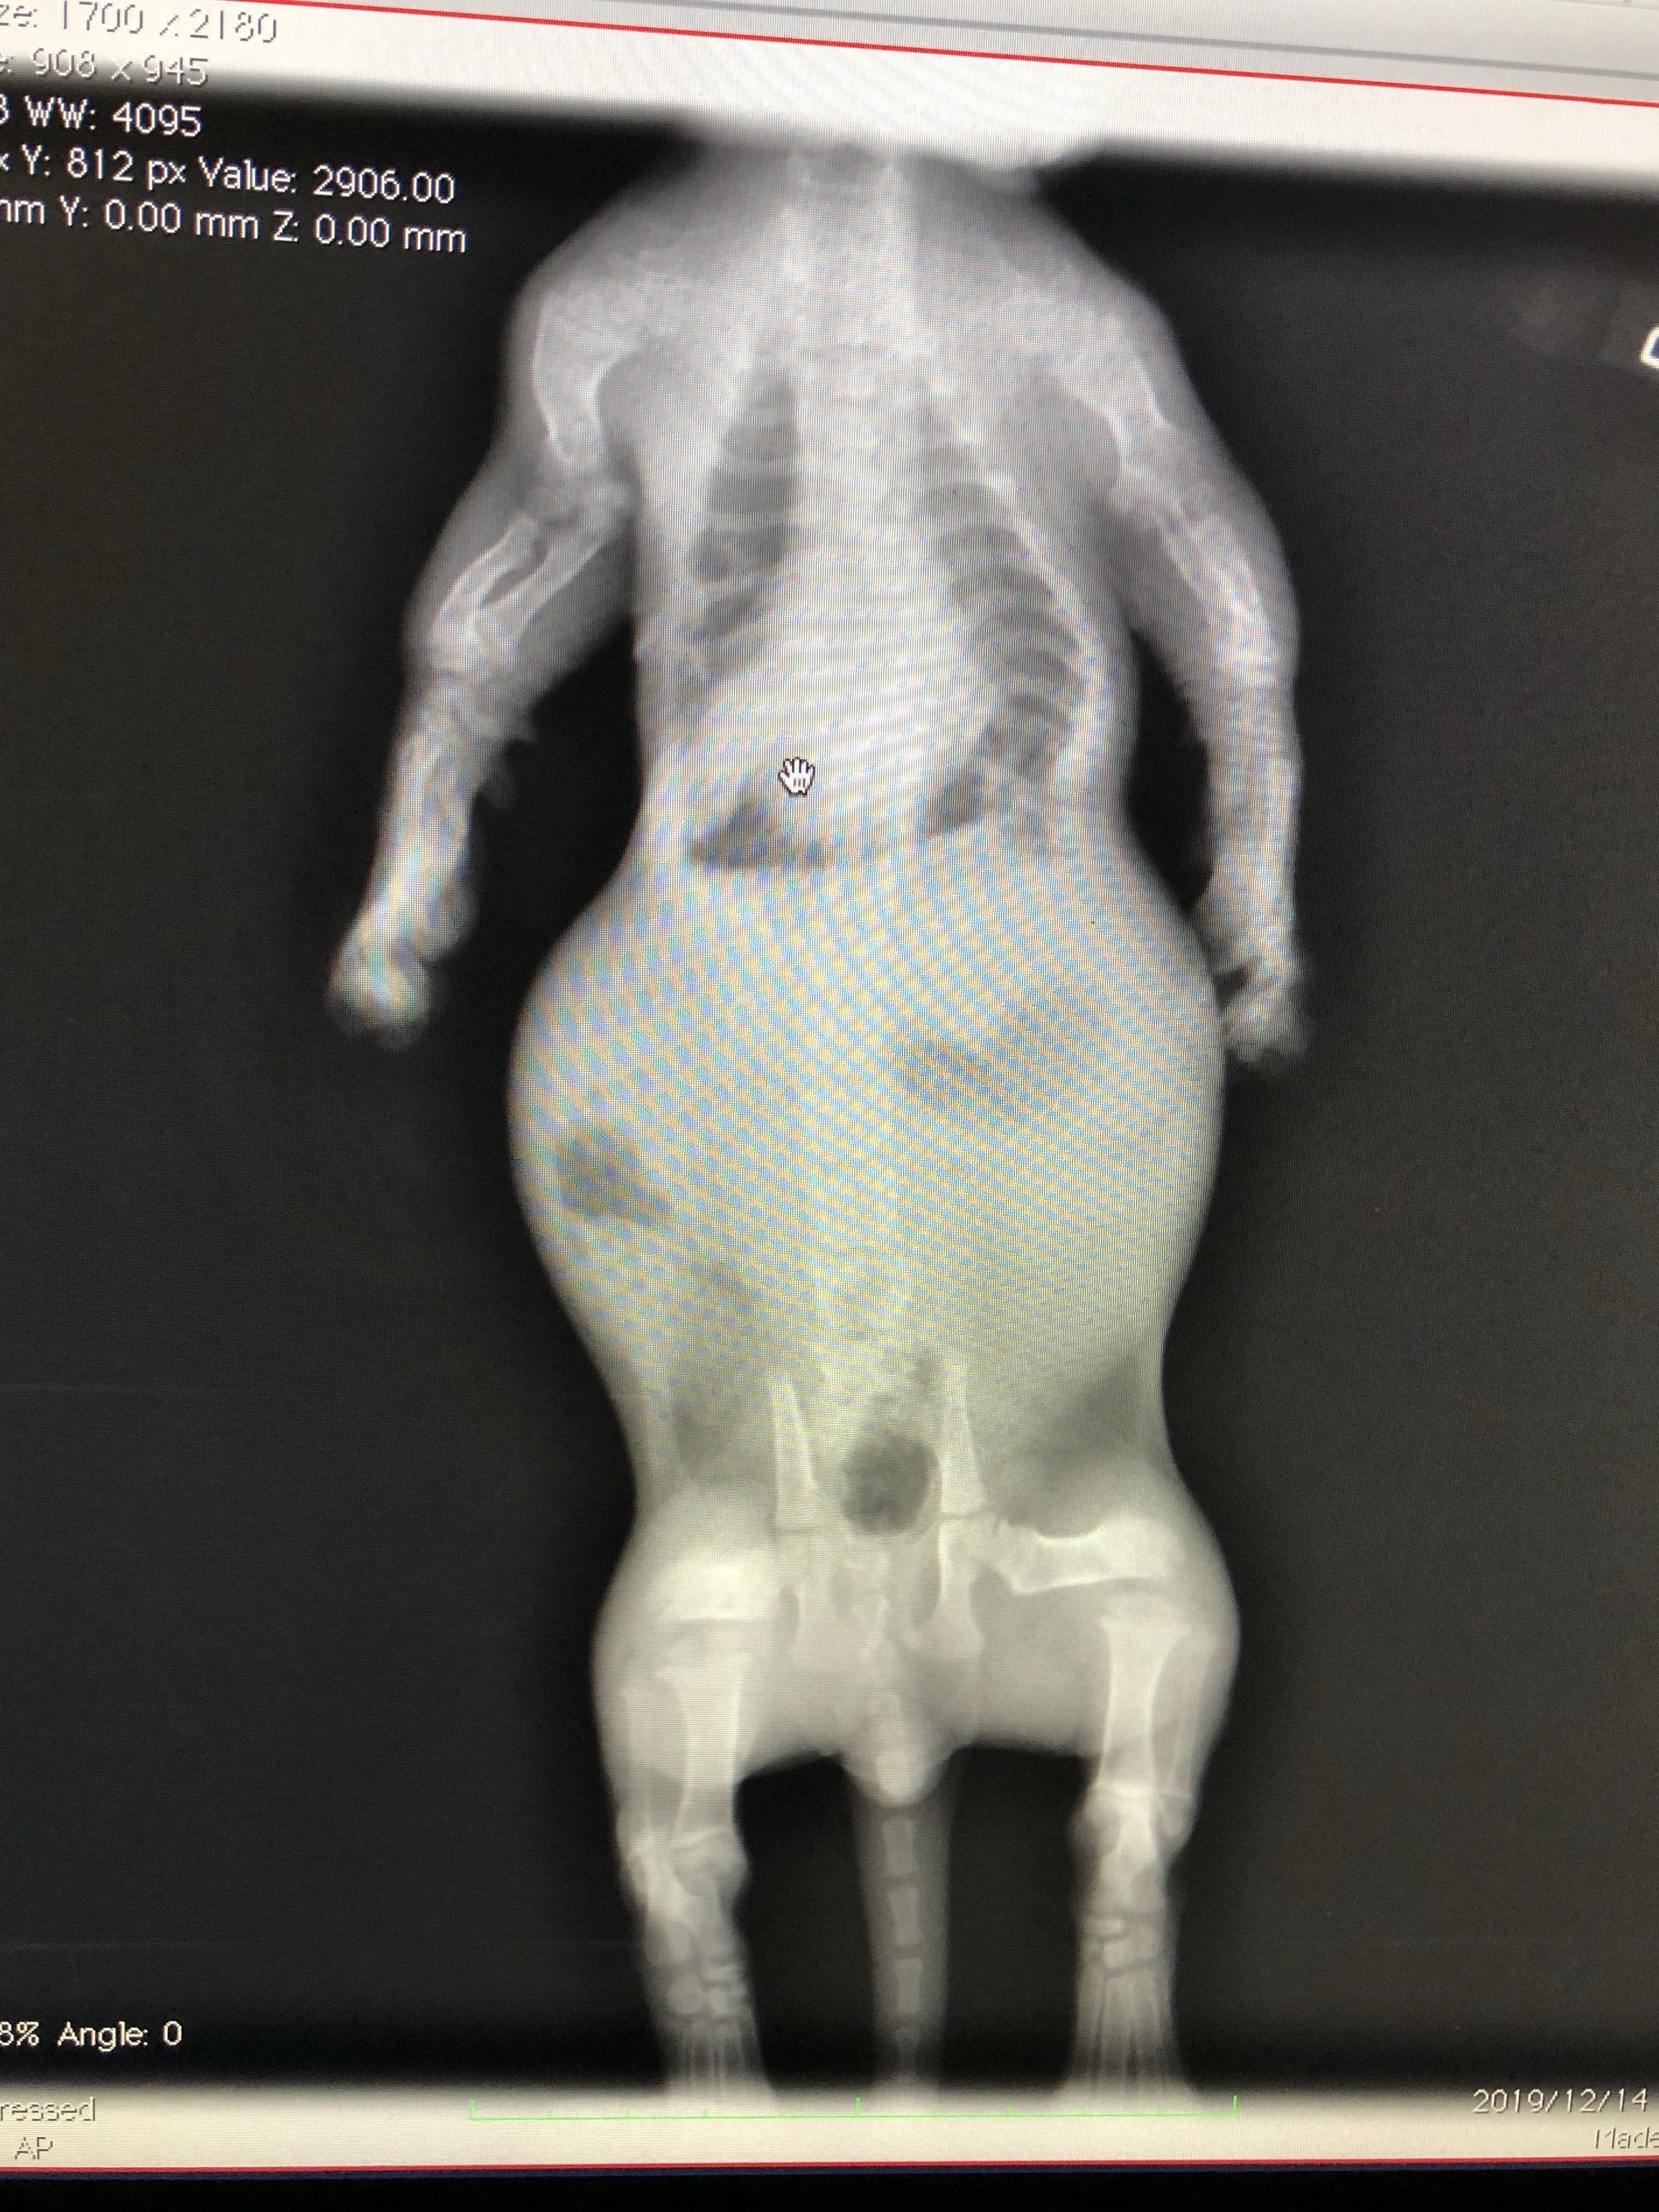

肋骨変形に伴う脊椎側変症

先天的な骨格異常で背骨と肋骨が変形していると診断されました。

また、この骨格異常により、肋骨と背骨の間のスペースが狭く、このまま成長していくと心臓と肺が圧迫され最悪生きられないと言われました。

検査費

レントゲン、CT撮影で費用が嵩む上、成長過程のため、複数回必要とのこと。これらを総合し、合計150万円〜は用意しておいて下さいと言われました。